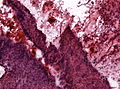

Features (papillary):[7]

- Non-keratinized squamous epithelium (without nuclear atypia).

- Fibrovascular cores (required for papillary).

Notes:

- +/-Cilia (rare).

- +/-Goblet cell-like formations (rare).